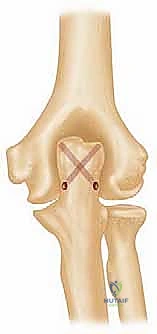

لفهم أهمية الجراحة التي يجريها الأستاذ الدكتور محمد هطيف، يجب أن نفهم أولاً طبيعة مفصل الكوع. يتكون الكوع من التقاء ثلاث عظام رئيسية:

1. عظم العضد (Humerus): العظمة العلوية للذراع، والجزء السفلي منها (البعيد) هو الذي يتعرض للتفتت في هذه الحالات.

2. عظم الزند (Ulna): العظمة الداخلية للساعد، والتي تشكل المفصل المفصلي (Hinge) مع العضد.

3. عظم الكعبرة (Radius): العظمة الخارجية للساعد، والتي تسمح بحركة الدوران (الكب والاستلقاء).

يحيط بهذا المفصل شبكة معقدة من الأربطة، والأوتار، والأعصاب الحيوية (مثل العصب الزندي، العصب الكعبري، والعصب المتوسط). عندما يحدث كسر مفتت في الجزء السفلي من عظم العضد، تتدمر الأسطح المفصلية الملساء تماماً. وإذا لم يتم استعادة هذا السطح الأملس بدقة متناهية، فإن النتيجة الحتمية هي احتكاك عظمي مؤلم، خشونة مبكرة، وفقدان دائم للحركة.